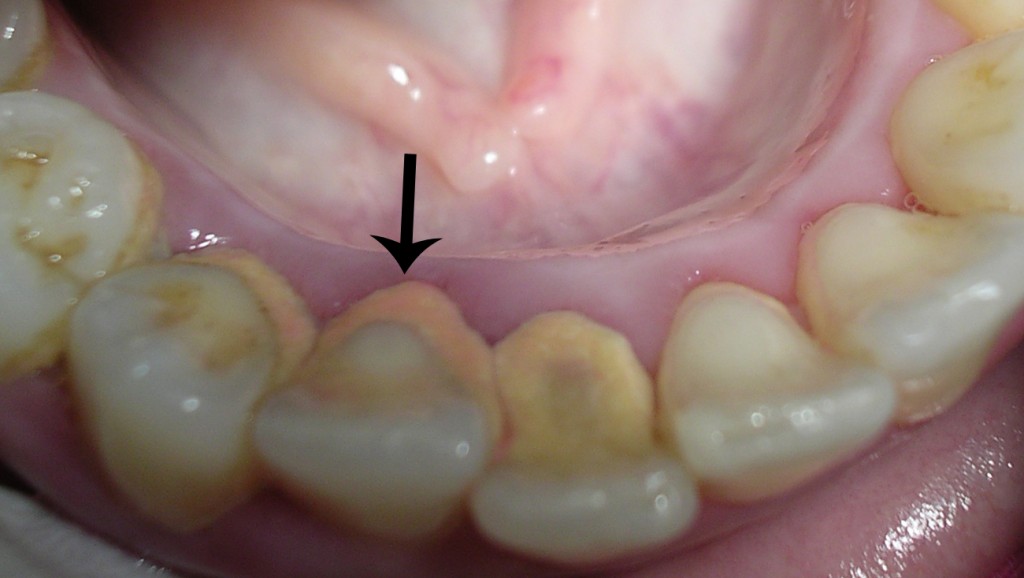

No obstante, a pesar de todo, es normal generar con el tiempo algo de sarro a nivel, sobre todo, de la cara externa de los primeros molares superiores y de la cara interna de los incisivos inferiores.